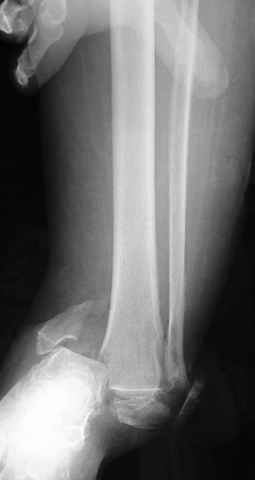

Дистракция в аппарате или на вытяжение результат - лигаментотаксис, посмотреть бы, как сегодня расположены отломки.

-Совершенно согласен артродез в остром периоде, нечем фиксировать и мягкотканые осложнения пугают любого. Выжидательная тактику рекомендовал бы для данного больного, через несколько месяцев после сращения всех фрагментов, если делать артродез, то будет на что лепить конструкцию.